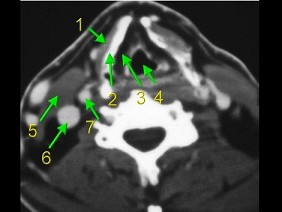

4.下面是一颈部CT图,其中结构标志不正确的是  (    )

正确答案:D